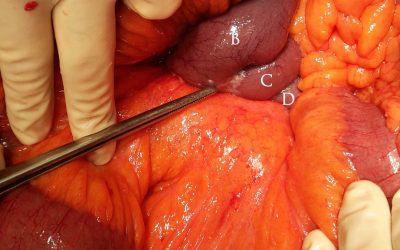

Fibrosi mesenterica correlata a tumore neuroendocrino (carcinoide) dell’intestino tenue

di Enrico Ganz La più nota e frequente sindrome paraneoplastica associata ai tumori neuroendocrini compresi tra la terza porzione duodenale e il colon trasverso prossimale (“midgut carcinoids”) è la sindrome da carcinoide, comprendente un’ampio spettro di...